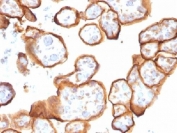

IHC testing of FFPE human placenta with Thrombomodulin antibody (clone THBD/1591). HIER: boil tissue sections in 10mM Tris buffer with 1mM EDTA, pH 9, for 10-20 min followed by cooling at RT for 20 min.